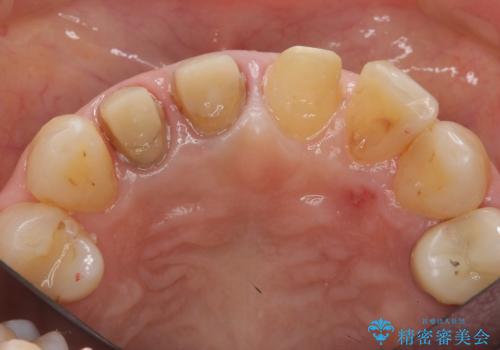

- 前歯のすき間を気にして来院。

右上2本を以前セラミックにしたが、前歯のすき間が広がってきてしまったとのこと。

右上の前歯二本、左上の前歯1本をセラミックにし、正中の前歯を2本連結しました。

連結しなくても、ナイトガード使用で防止できると説明しましたが、手間をかけずに二度と広がらない方がいいとのことで連結を強くご希望でした。

歯周病や楽器の影響などですき間が生じることはありますが、今回は開いてきた原因はわからないため、連結するか、ナイトガードをはめて歯ぎしりで力がかかりすぎないようにすることが大事になってきます。